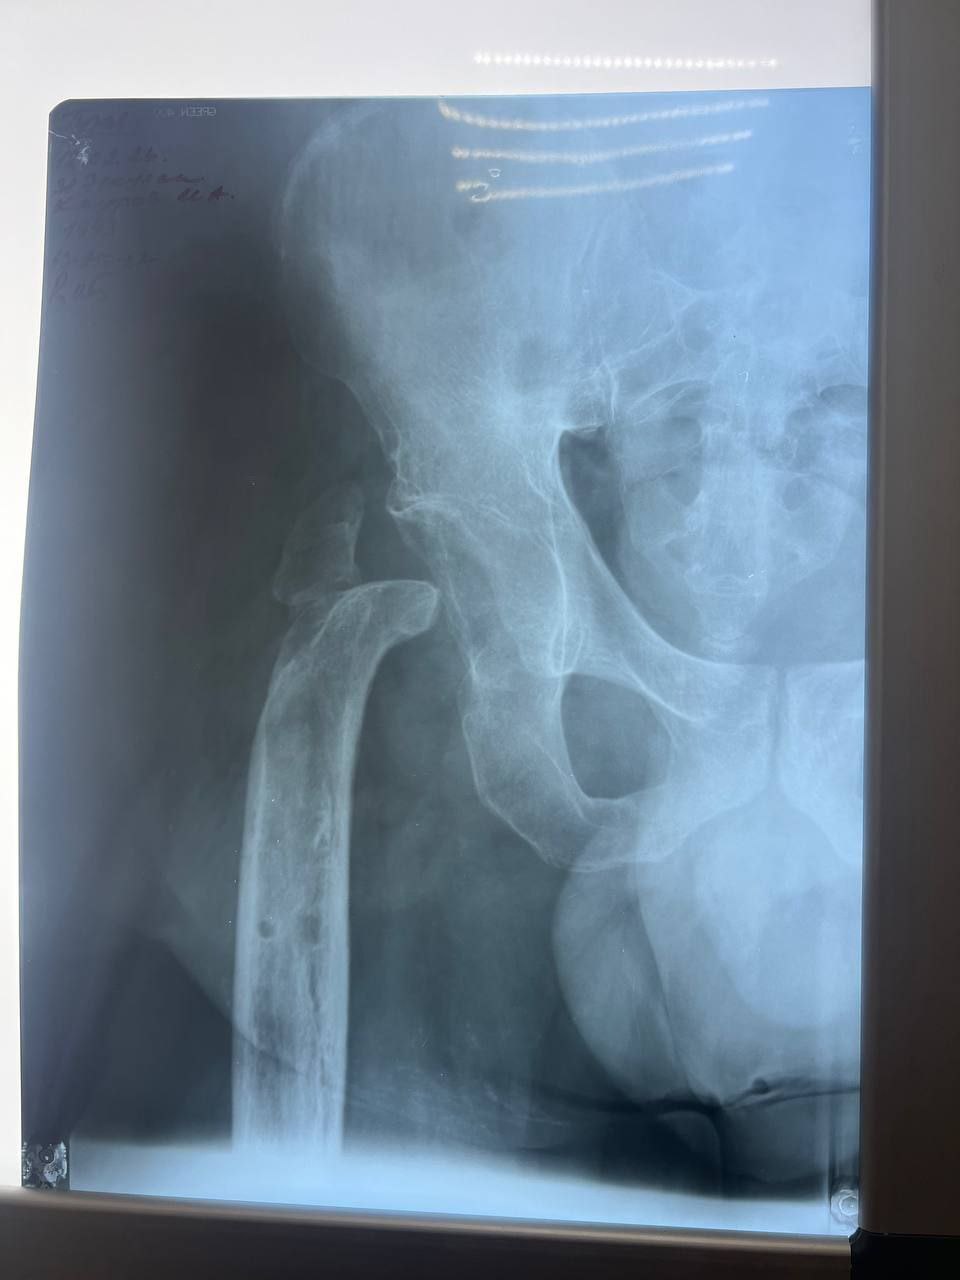

Из-за обширных повреждений и многократных операций правая нога бойца стала короче левой на 8-9 сантиметров. Обычное эндопротезирование здесь было бессильно. Требовалось чудо инженерной и хирургической мысли.

Вместо стандартной замены сустава пациенту выполнили сложнейшее вмешательство с использованием ревизионных систем эндопротезирования, в ЛНР такую операцию провели впервые. Главная задача хирургов заключалась не просто в установке импланта, а в восстановлении биологической оси конечности и компенсации укорочения.

Хирургам пришлось работать в рубцово-измененных тканях после десятка предыдущих операций, убрать очаги инфекции (некроэктомия) и с помощью специальных ревизионных компонентов буквально «собрать» сустав заново, вернув ноге физиологическую длину. Для пациента это означает шанс не просто избавиться от боли, но и забыть о хромоте, вернуться к нормальной походке.

05.03.2026 — Эндопротезирование тазобедренного сустава ревизионными системами с восстановлением оси и длины конечности.